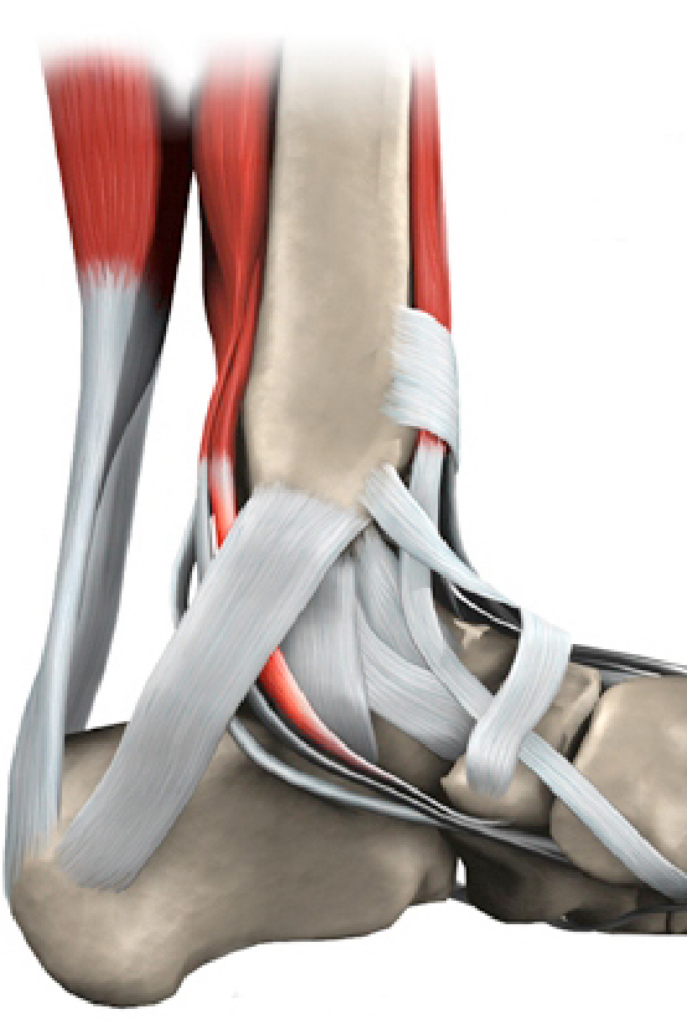

The tibialis posterior (TP) tendon is one of the major stabilising structures in the foot. It runs behind the bump on the inside of the ankle (the medial malleolus) and inserts into one of the bones of the instep (navicular). The main functions of the tendon are to support the arch and keep the foot turned inwards when walking. The TP can become damaged by wear and tear or acute trauma.

In most cases the tendon itself is not able to be repaired and needs to be strengthened by using a near-by tendon which functions to flex the toes and this is transferred from the foot. Other tendons help to carry out this function so loss of this tendon rarely results in problems.

To improve the biomechanics of the tendon transfer the heel bone is moved towards the inside of the foot (calcaneal osteotomy) and held with screw fixation. In addition, a plug may is inserted into the outer portion of the foot to assist in supporting the arch. If required the plug and/or screws can be removed in a second operation when they have served their purpose and the tendon is healed. Additional procedures such as synthetic tissue augments, lengthening of the achilles tendon and other bony surgery may be required and will be discussed if thought necessary.